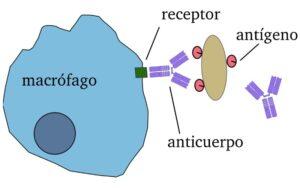

Opsonización